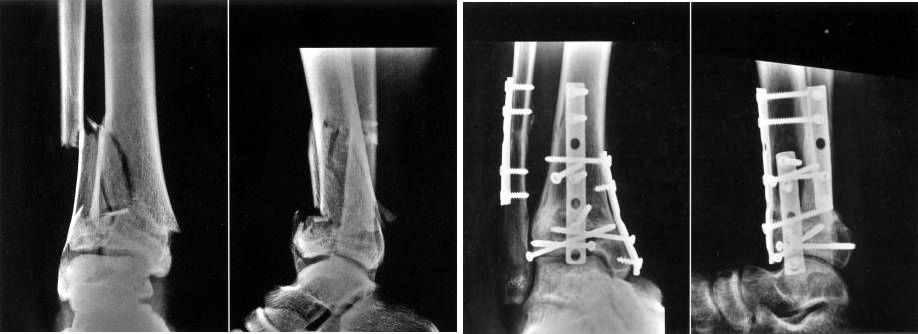

Перелом лодыжки внутрисуставной.

Целью лечения является восстановление нормального анатомического строения суставов.

Сроки операции зависят от состояния мягких тканей.

Идеальное время для операции – до появления отека и волдырей в области перелома.

Это опора для людей, чтобы стоять и ходить.Восстановление нормальной анатомической структуры стопы играет жизненно важную роль в процессе стояния и ходьбы.

Как и при переломах лодыжки, сроки операции зависят от степени и состояния отека мягких тканей.